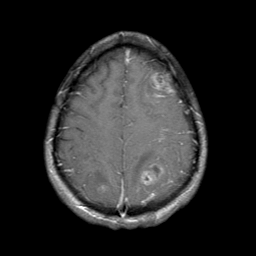

Sarcoma, MR Study #1 mr-gad -- Slice #19

[Home][Help][Clinical] Slice 19